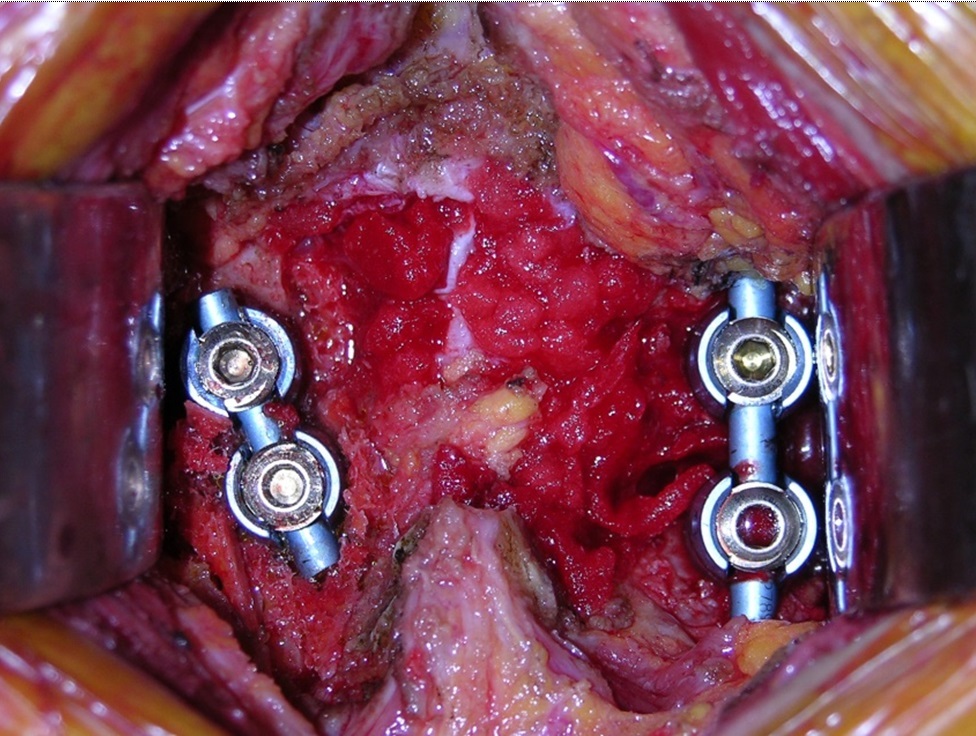

Hình ảnh minh họa

tủy sống được giải phóng chèn ép tốt